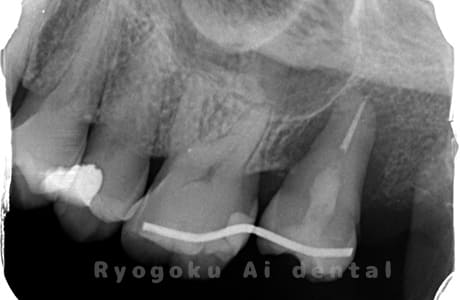

Case02

-

- 原因

- C4

- 治療期間

- 3ヶ月

- 治療内容

- 自家歯牙移植手術+マイクロエンド+ダイレクトボンディング

- 治療費用

- 220,000円

他院で虫歯が大きく、抜歯と判断され、インプラント手術を提案された患者様です。親知らずが残存していたため、自家歯牙移植手術を行いました。

<リスク・副作用>

治療後、痛みや違和感、出血、腫れなどが出る事があります。喫煙者、糖尿病などの方の場合、歯が生着しない場合があります。